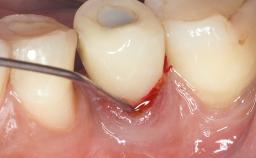

In this case, Myroslav Solonko, Ignacio Sanz Sánchez and Mariano Sanz present a treatment that aims to eliminate exposed implant threads by modifying the implant surface, converting a moderately-rough surface into a smooth surface.

A 63-year-old male patient was referred to the post-graduate periodontal clinic of the Complutense University of Madrid for the treatment of peri-implantitis. According to the patient’s record, all his maxillary teeth had been extracted ten years previously due to severe periodontitis, and a full-mouth implant-supported restoration on eight implants was placed. No supportive periodontal therapy was provided apart from occasional check-ups by the restorative dentist.